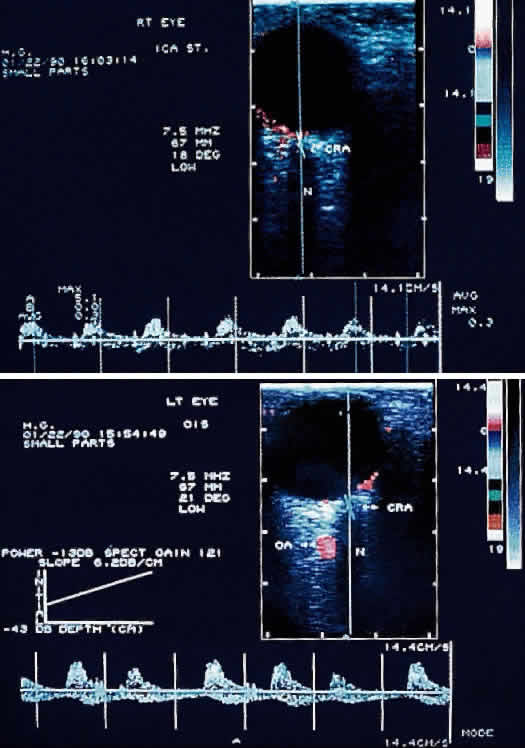

ORBITAL COLOR DOPPLER IMAGING

Orbital color Doppler imaging is a noninvasive ultrasound test that permits simultaneous imaging of small orbital vessels and recording of quantitative data on blood flow velocity. Unlike duplex carotid ultrasonography, which images and measures flow velocity in the large carotid vessels, orbital color Doppler imaging can image the smaller ophthalmic, central retinal, and short posterior ciliary arteries.28

With the use of orbital color Doppler imaging, the central retinal and posterior ciliary artery peak systolic velocities have been reported to be markedly reduced in ocular ischemic syndrome, as would be expected (Fig. 8).13 Reversal of ophthalmic artery blood flow, which probably represents collateral blood flow to lower resistance vascular beds, was detected in 75% of eyes with ocular ischemic syndrome. It is interesting to note that although high-grade carotid stenosis, reversal of ophthalmic artery flow, and decreased central retinal artery flow have been associated with ocular ischemic syndrome, this combination in and of itself has not been sufficient to routinely produce decreased vision. Absence of detectable posterior ciliary arterial blood flow was the only reliable indicator of poor vision.

Fig. 8. Color Doppler imaging study of the central retinal artery in an eye with ocular ischemic syndrome (left). Areas in red superimposed on the B-scan image depict blood flow moving toward the transducer, mostly representing arterial flow. Areas in blue depict flow, mostly venous, away from the transducer. Notice the reduced systolic peaks of the time-velocity waveform (graph below the B-scan image) in contrast to the normal pattern of the uninvolved contralateral eye (right). (Ho AC, Lieb WE, Flaharty PM et al: Color Doppler imaging of the ocular ischemic syndrome. Ophthalmology 99:1453, 1992)

One limitation of orbital color Doppler imaging is its inability to measure volumetric blood flow directly; rather, this study modality relies on measurements of peak systolic blood flow velocity and vascular resistance, which in most physiologic situations are gauges of blood flow. Currently, orbital color Doppler imaging is most useful as an investigational technique for studying the hemodynamics of ophthalmic vascular disorders. In the future, it may provide useful information for the diagnosis and management of ocular ischemic syndrome.